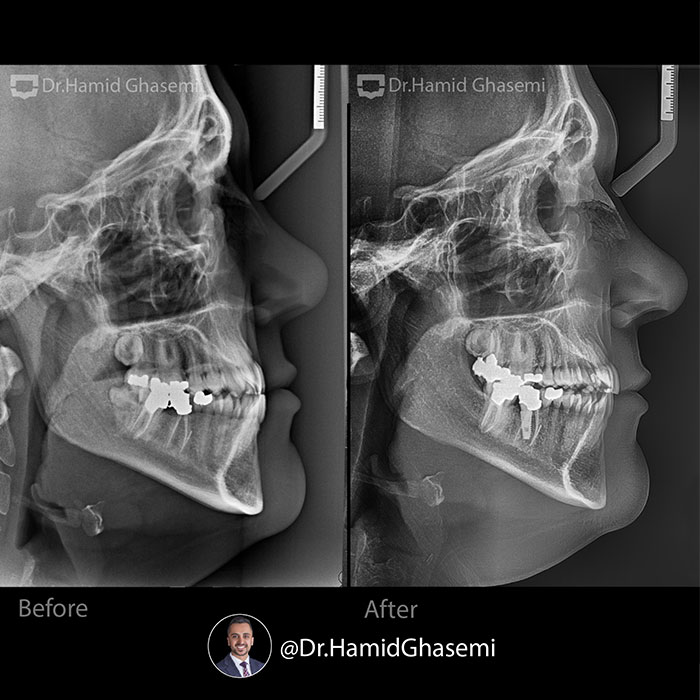

️Non surgical orthodontic treatment of class 3 case (32 years old) with constricted maxilla and retruded maxilla done within 22 months. Hyrax bone expander with palatal screws used in order to expand upper arch. Minimal advancement of upper arch which is been due to indirect effect of expansion is obvious in lateral cephalo xrays (comparing point A from pre and post lateral ceph xrays). In lower arch lower wisdome teeth were extracted and minimal retraction done using screws as well.